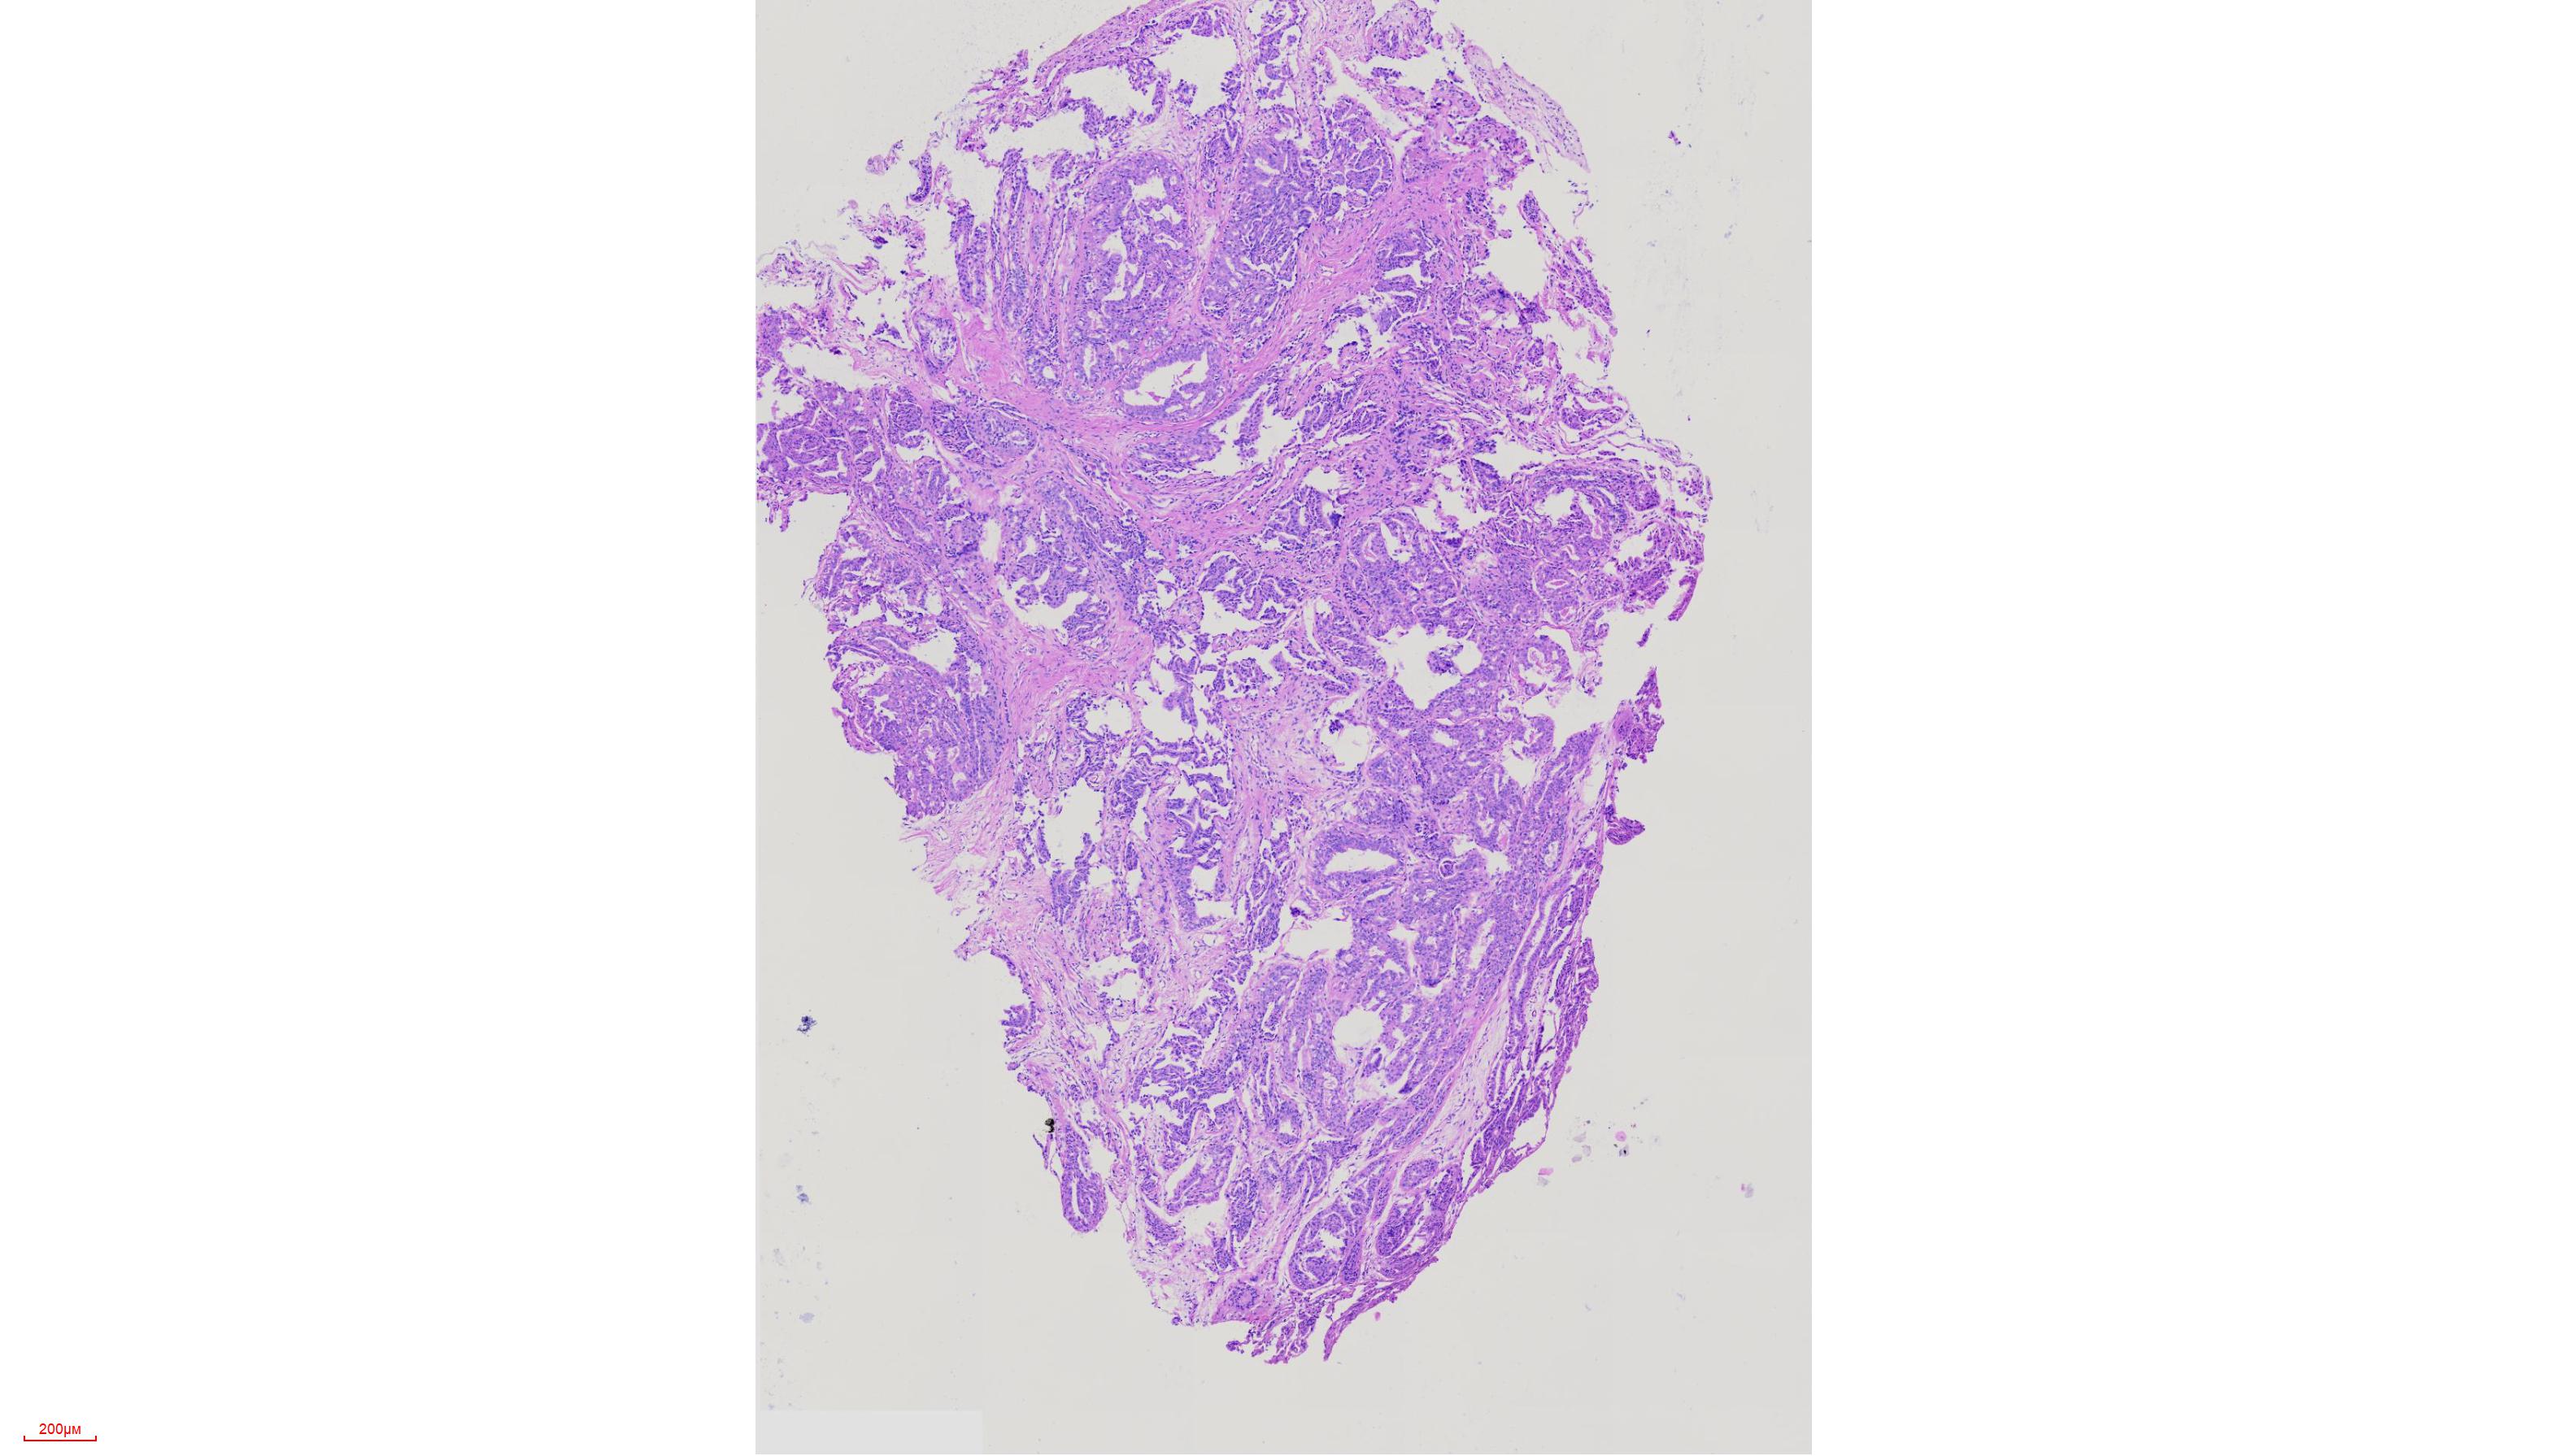

外阴肿物

性别

女

年龄

51岁

外阴肿物一年余

灰白色黄豆大组织

考虑为生乳头状汗腺瘤